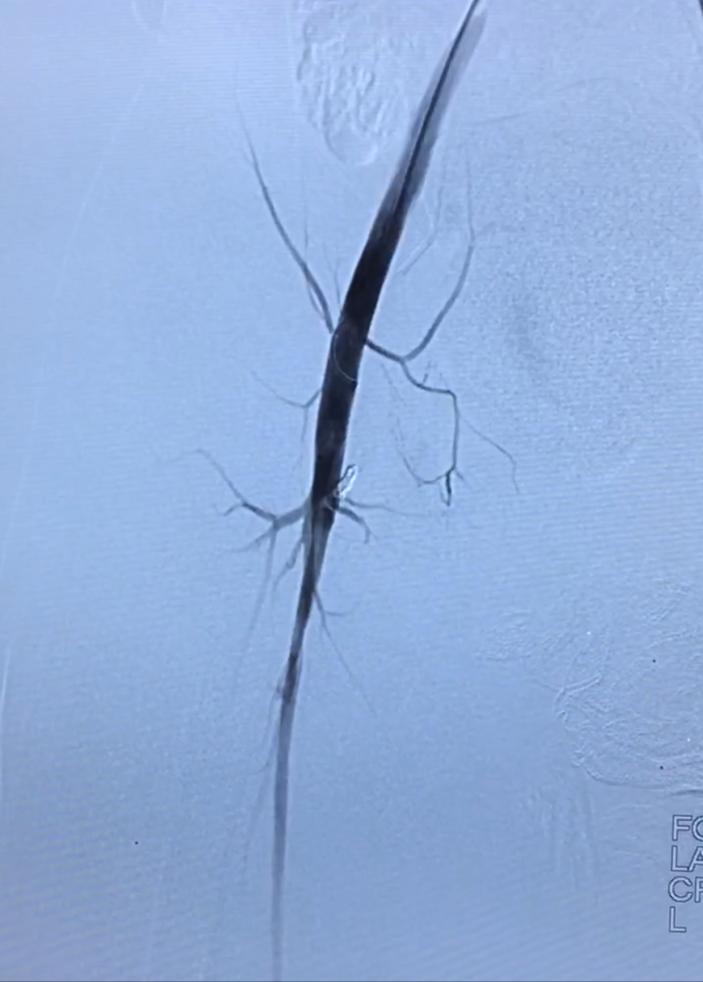

和家长沟通确定治疗方案后,孩子全麻下,穿刺股动脉,把导管置入右下肢血管行造影,术中造影看到特别明确的股动静脉瘘,瘘道长度及宽度和术前评估相似,决定弹簧圈栓塞,没想到困难重重,动脉端难超选,角度太小,母管固定难,小的弹簧圈站不住,无法成圈,大弹簧圈稍长又脱出。

又试静脉端,照样难固定。经历了无数脱管,再超选,反复尝试,原本一个小时手术已经超过3个半小时,奇迹出现,多次尝试后终于让弹簧圈站稳了,位置恰恰好,瘘道完全栓塞。回病房后患儿卧床12小时,第二天就可以下床,出院。

介入术中造影可见瘘口,弹簧圈栓塞后消失